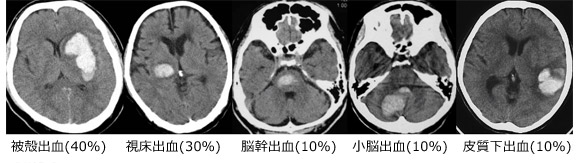

上記は、いろんな場所におこった脳出血のCTを呈示いたしました。脳出血は脳のあらゆる場所でおこることが知られています。場所によっておこる頻度も異なります。左側から頻度が多い順番に並べています。

また脳出血に決まった症状はなく、出血した部位、出血量、年齢などによって様々な症状が出現します。具体的には意識障害、片麻痺、感覚障害、視野障害、失語、構音障害といった症状です。